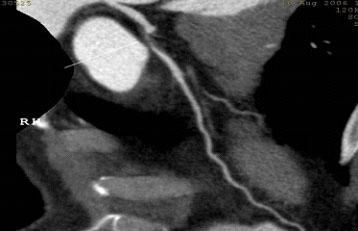

64排螺旋CT冠狀動脈血管成像:

1、簡單:無需經動脈插管,隻需象平時靜脈輸液一樣在肘靜脈内推注相對适量對比劑,然後行快速掃描即可完成整個檢查。

2、安全:64排螺旋CT冠狀動脈造影,對比劑用量較少,無需動脈插入導管,患者無需承擔麻醉及動脈插管等帶來并發症的危險。在冠狀動脈血管疾病的篩查、早期診斷、冠狀動脈成形術和搭橋術前、術後血管評價,冠狀動脈起源異常及心肌橋等方面極具優勢。

3、後處理功能豐富:西門子公司爲SOMATOM Definition AS+ 128層4D螺旋CT配備了功能強大的後處理工作站:MMWP(多産品工作站)和最新型的醫學影像IT工作平台,Syngo.via,智能,便捷。

CT冠脈血管成像:

1.冠脈軟斑塊:

2.混合性斑塊:

3.對于斑塊性質的确定,CT優于DSA: